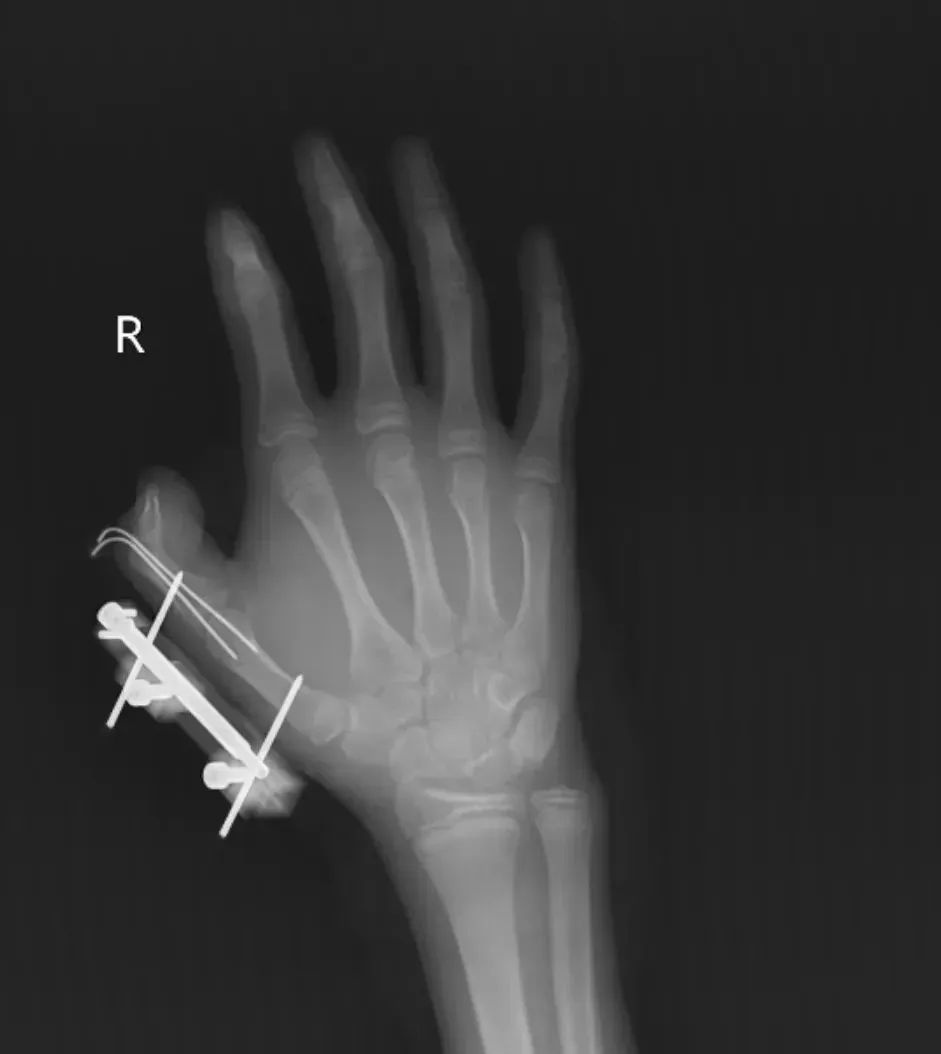

突然,密封袋里的干冰发生爆炸。维维的右手瞬间鲜血直流,拇指虎口处被撕开一道约10厘米的伤口,肌肉组织断裂外露,还伴随拇指骨折、关节脱位,整个拇指完全失去知觉。

经治疗

维维的拇指保住了

但后续还需长期康复训练

才能慢慢恢复手部精细动作功能